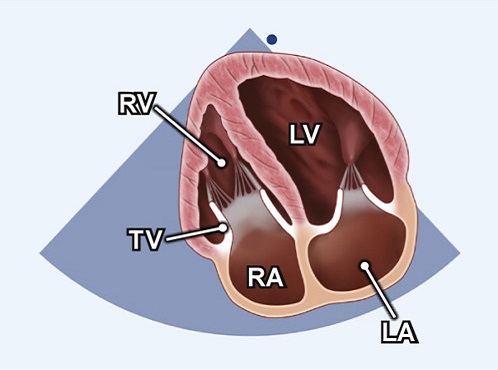

A4C RV focused (Echo) - TECHmED